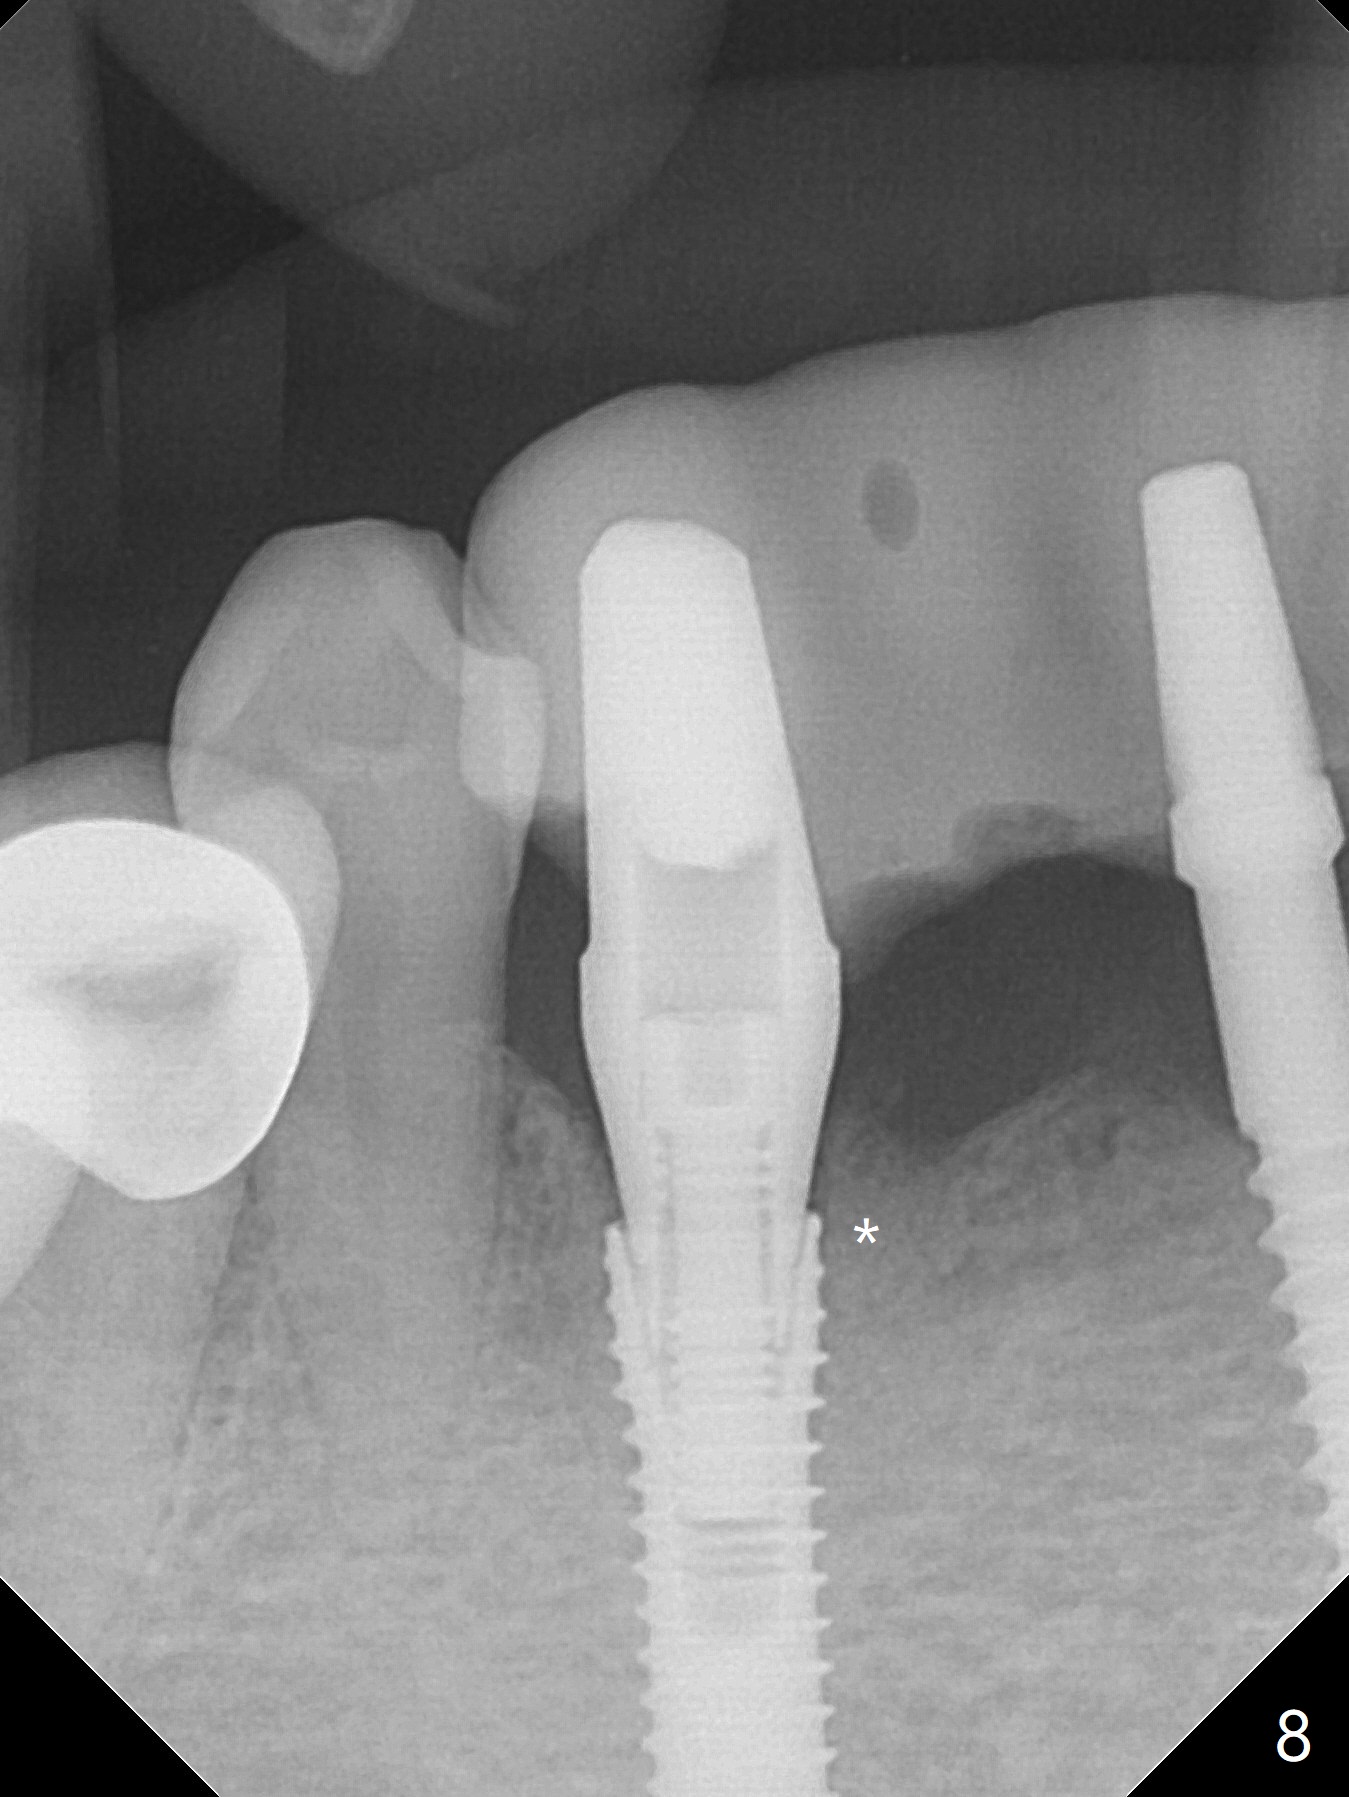

The mesial defect at #27 appears to have been repaired 8 months postop (Fig.8,9 *); there is no bone loss at 1-piece implant sites. The gingival recession seems to remain the same before and after removal of the provisional FPD (Fig.10,11). The bulging abutment at the cervix is less prominent when a straight abutment is used and prepared (Fig.12, 4.5x5.5(5) mm). There is no bone loss at #23, 25 and 27 sites 2.5 years post cementation (Fig.12-15), although the trajectory of the implants could be improved by using surgical guide (Fig.16-18).